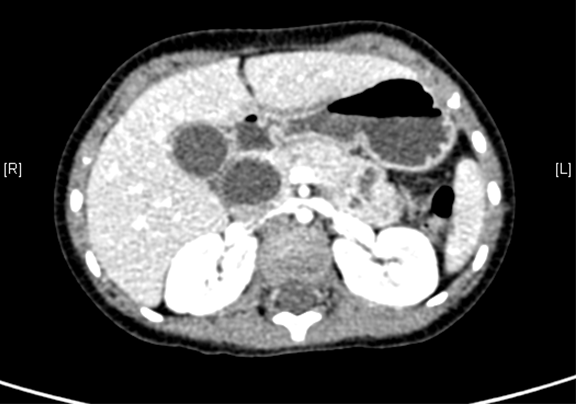

术前CT检查:

静脉期

上腹部增强CT:1. 胆总管囊肿、肝内胆管略扩张2. 胆囊壁厚,考虑胆囊炎可能性大。